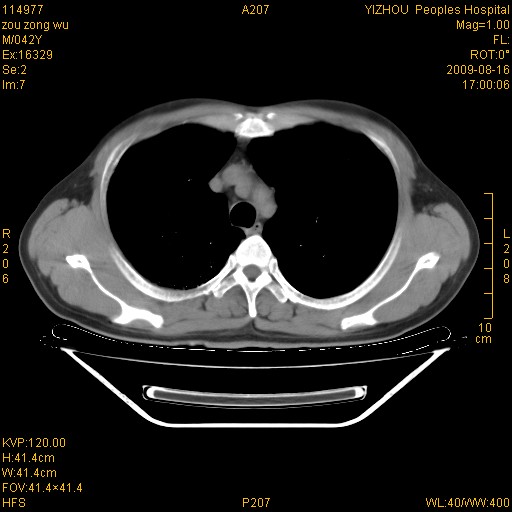

以下是引用zjzjr在2009-8-17 10:42:00的发言:[br]右侧间质性肺炎伴纤维化,右肺下叶肺囊肿伴感染(不除外外伤后引起),右肺野及胸壁软组织\\肝内见多发斑点状,中枪了吧.右侧胸膜肥厚\\粘连.